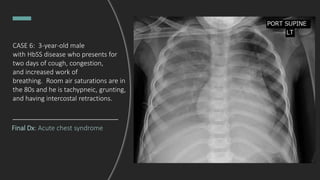

CASE 6: 3-year-old male

with HbSS disease who presents for

two days of cough, congestion,

and increased work of

breathing. Room air saturations are in

the 80s and he is tachypneic, grunting,

and having intercostal retractions.

Interpret this chest x-ray.

Bilateral opacities, right > left with air

bronchograms. Moderate right sided

pleural effusion. Overlying high flow nasal

cannula.

DDx: pulmonary edema, multifocal

pneumonia

Final Dx: Acute chest syndrome